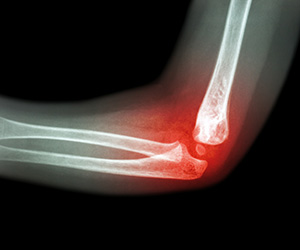

Elbow Fracture Reconstruction

Elbow fracture reconstruction is a surgical procedure employed to repair and restore the appearance and full function of a damaged elbow caused by severe trauma or injury.

Distal Humerus Fractures of the Elbow

Injury in the distal humerus can cause impairment in the function of the elbow joint.

Radial Head Fractures of the Elbow

Radial head fractures are very common and occur in almost 20% of acute elbow injuries.